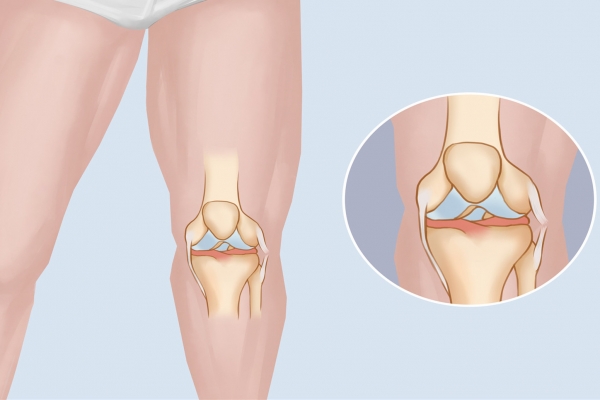

3.僵硬和活动受限

受伤部位的肌肉可能会变得僵硬,导致活动范围受限。比如腿部肌肉拉伤后,走路时可能会感到不便,手臂肌肉拉伤后,抬手或伸手时会感到困难。